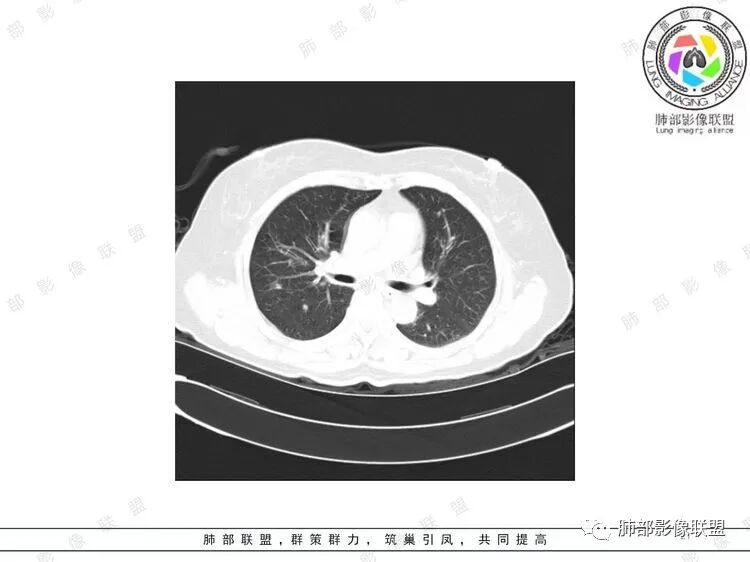

胸CT:双中下肺支气管壁明显增厚,双下肺胸膜下可见实变区。部分病变呈楔形影。

老年女性,咳嗽咳痰低热20天,双肺野散在结节影,随机分布,双肺下叶支气管血管束增粗,支气管管腔狭窄,胸膜下结节斑片影,临床有血尿,痰培养白念阳性,低氧血症。血管炎抗体阴性。从影像看主要侵犯的是血管,血管壁增厚,血管炎抗体阴性不大支持,患者有血尿,考虑膀胱肿瘤引起转移,但是膀胱彩超没发现占位,估计血尿是膀胱炎引起。从影像看考虑侵袭性曲霉菌病?血管炎?实在没有思路。

双肺多发大小不等结节,周围伴有晕征,边界模糊,部分结节内似可见支气管影,双肺血管束明显比支气管增粗,临床有感染症状,考虑GPA,疱疹病毒。

双肺支气管管壁弥漫性增厚,管腔狭窄,下叶为主,伴多发高密度结节影,边缘模糊,双肺支气管血管束明显增粗,临床症状咳嗽低热,有血尿,首先考虑血管炎

支气管壁增厚,两下肺为主,沿支气管血管束分布斑片状、结节状病变,中轴间质增厚。疾病谱可能有:1.气道来源疾病:结核、曲霉、支原体等;2.间质来源疾病:血管、淋巴系统。结合有血尿,使用激素后尿色变淡、抗生素治疗效果差等病史,考虑血管炎可能性大。

影像上:多发结节沿血管分布;双下叶支气管血管束简直增厚,偏血管,支气管通畅

因为支气管壁增厚,远端应该小气道病变,这个不是,反而是血管增粗明显

加上结节的分布,支持血管相关病变

两肺多发结片影,这个病灶很小,但是中间可见支气管影,支气管炎一般不会包在支气管周围,支气管周围间质可能大,包括血管,淋巴等。一般支气管这样穿行的,被包绕的,血管炎,淋巴瘤等这种间质起源比较多见

提示一个支气管周围的间质性病变,并且形成肉芽肿